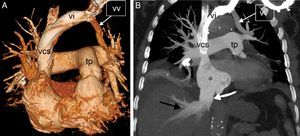

The patient was a 76-year-old woman with no significant medical history who consulted due to progressive dyspnea, edema in the lower limbs, and discomfort in the chest and abdomen. Chest radiography showed cardiomegaly and scant bilateral pleural effusion. Signs of right heart overload were observed on electrocardiogram, and D-dimer was slightly elevated. A chest CT angiogram ruled out pulmonary thromboembolism, but unexpectedly revealed a PAPVR in which the veins of the left upper lobe drained to the brachiocephalic vein via a vertical vein (Fig. 1A). Radiological signs of severe PAH were also observed, with dilation of the right heart cavities and congestion of the inferior vena cava and the suprahepatic veins (Fig. 1B).

(A) Computed tomography with 3D volume rendering showing a vertical vein (vv), formed by the confluence of pulmonary veins of the left upper lobe, running toward the brachiocephalic vein (vi); tp: pulmonary artery trunk; vcs: superior vena cava. (B) Coronal computed tomography with maximum intensity projection (MIP) showing signs of arterial/precapillary pulmonary hypertension and tricuspid valve insufficiency: dilation of right atrium (asterisk), inferior vena cava (white arrow) and suprahepatic veins (black arrow) congestion. Note the vertical vein (vv), the brachiocephalic vein (vi), and the superior vena cava (svc).